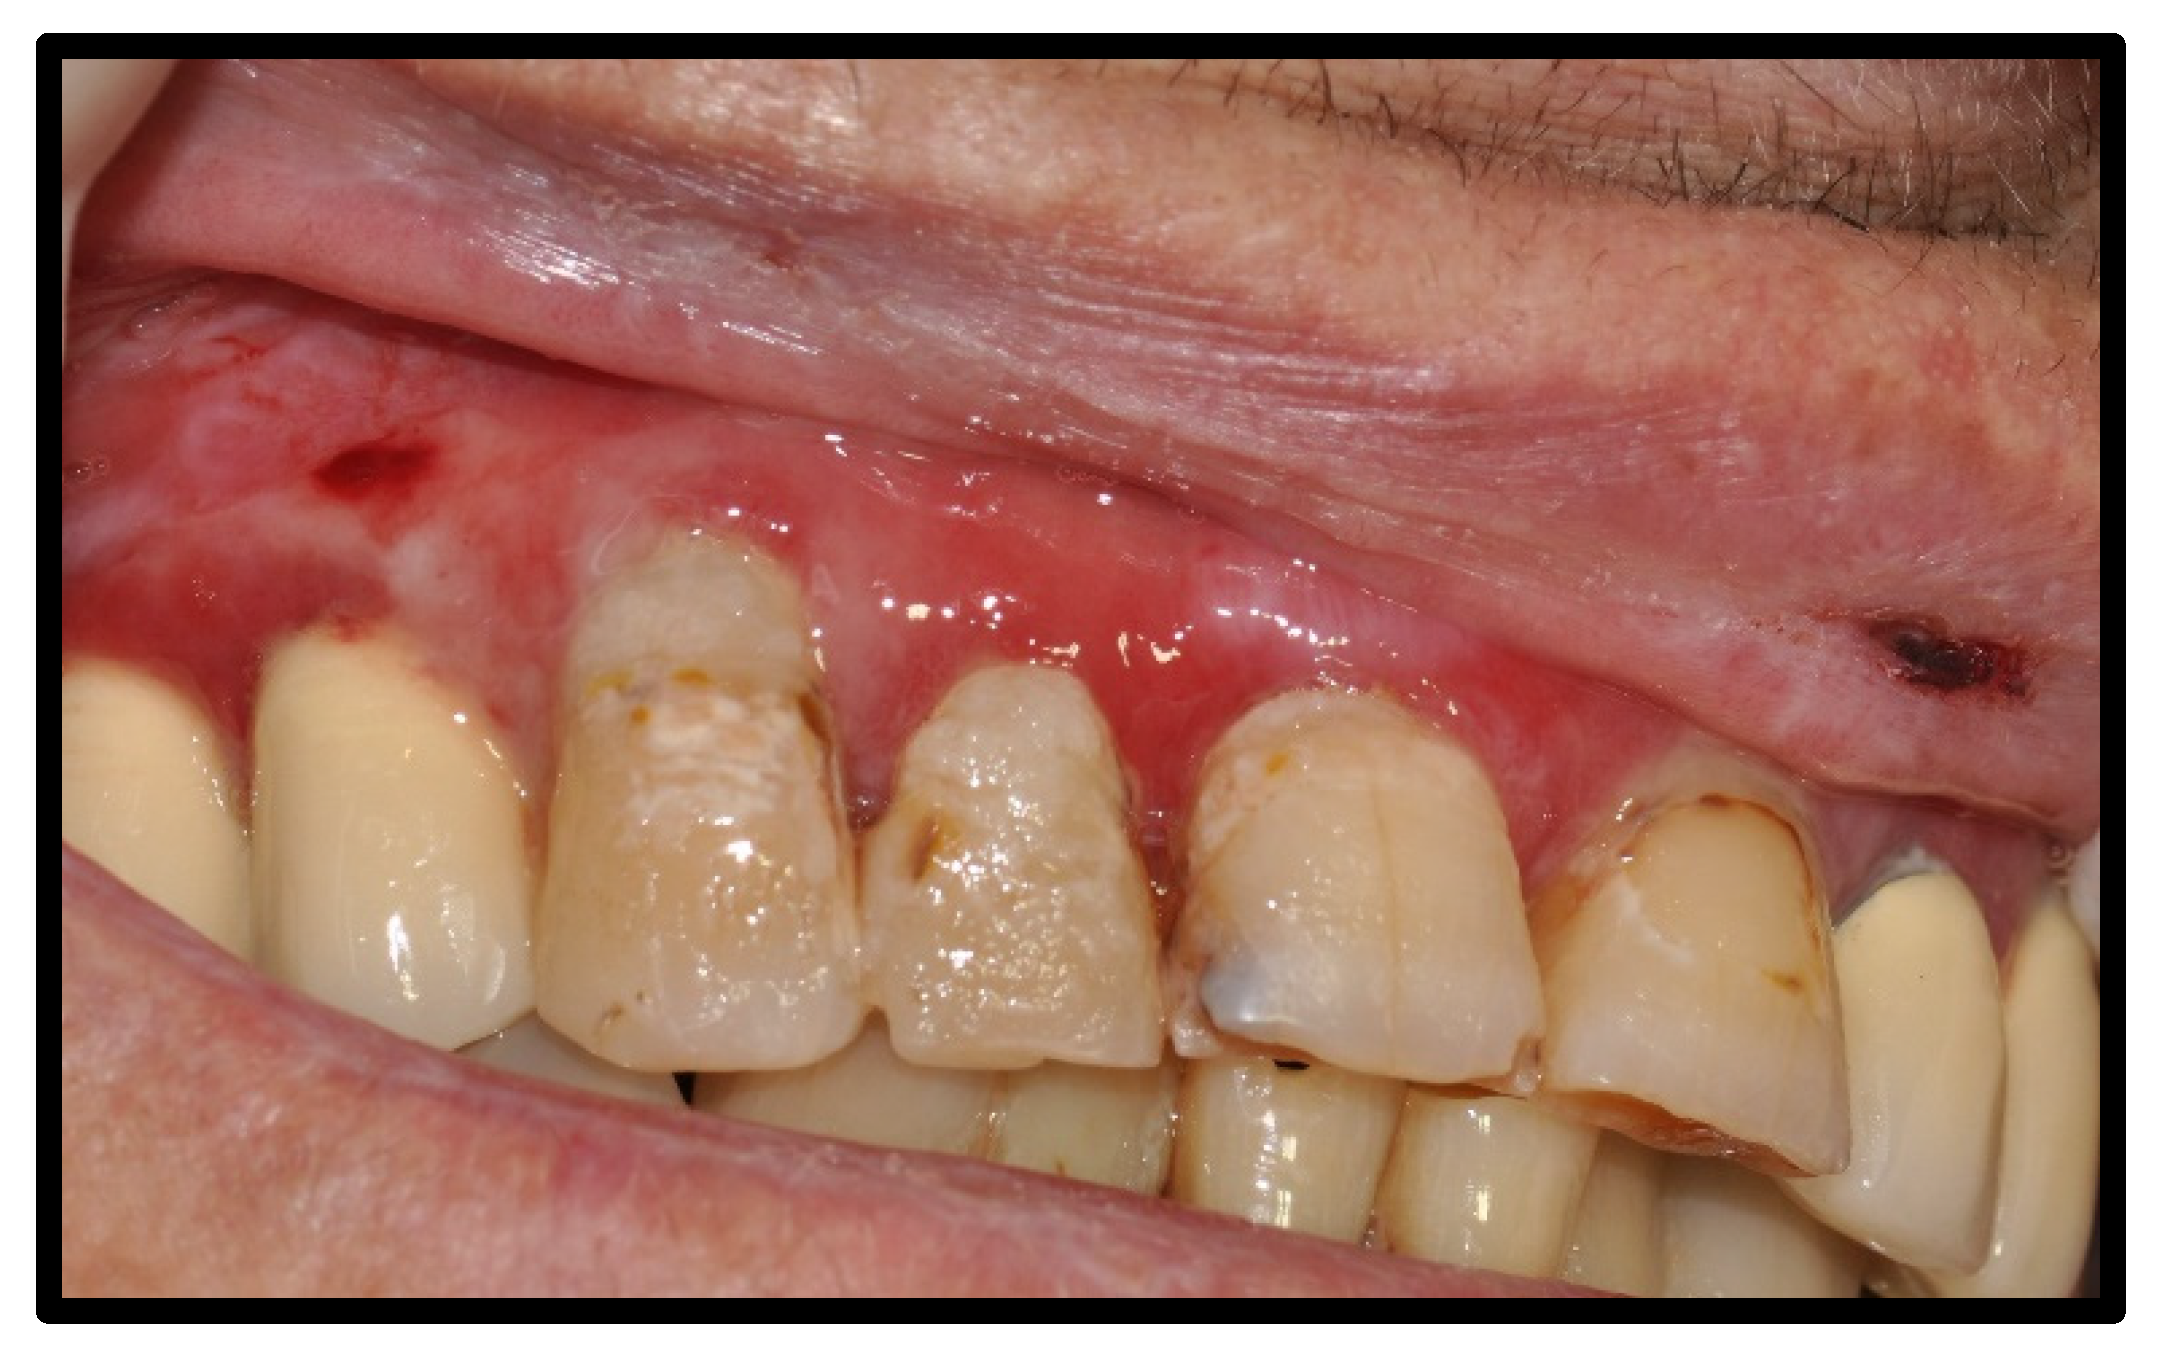

| Osteonecrosis of the mandible, exposed type | 6 | 25.00 | |

| Medications with known ONJ risk, prior or concurrent with Immunotherapy | |||

| Prior bevacizumab | 1 | ||

| Concurrent zoledronic | 1 | ||

| Prior sunitininb, followed by cabozantinib, concurrent denosumab | 1 | ||

| Concurrent bevacizumab & zoledronic acid | 1 | ||

| Prior & concurrent zoledronic acid | 1 | ||

| Concurrent denosumab | 1 | ||

| Management | Conservative, antibiotics | 6 | |